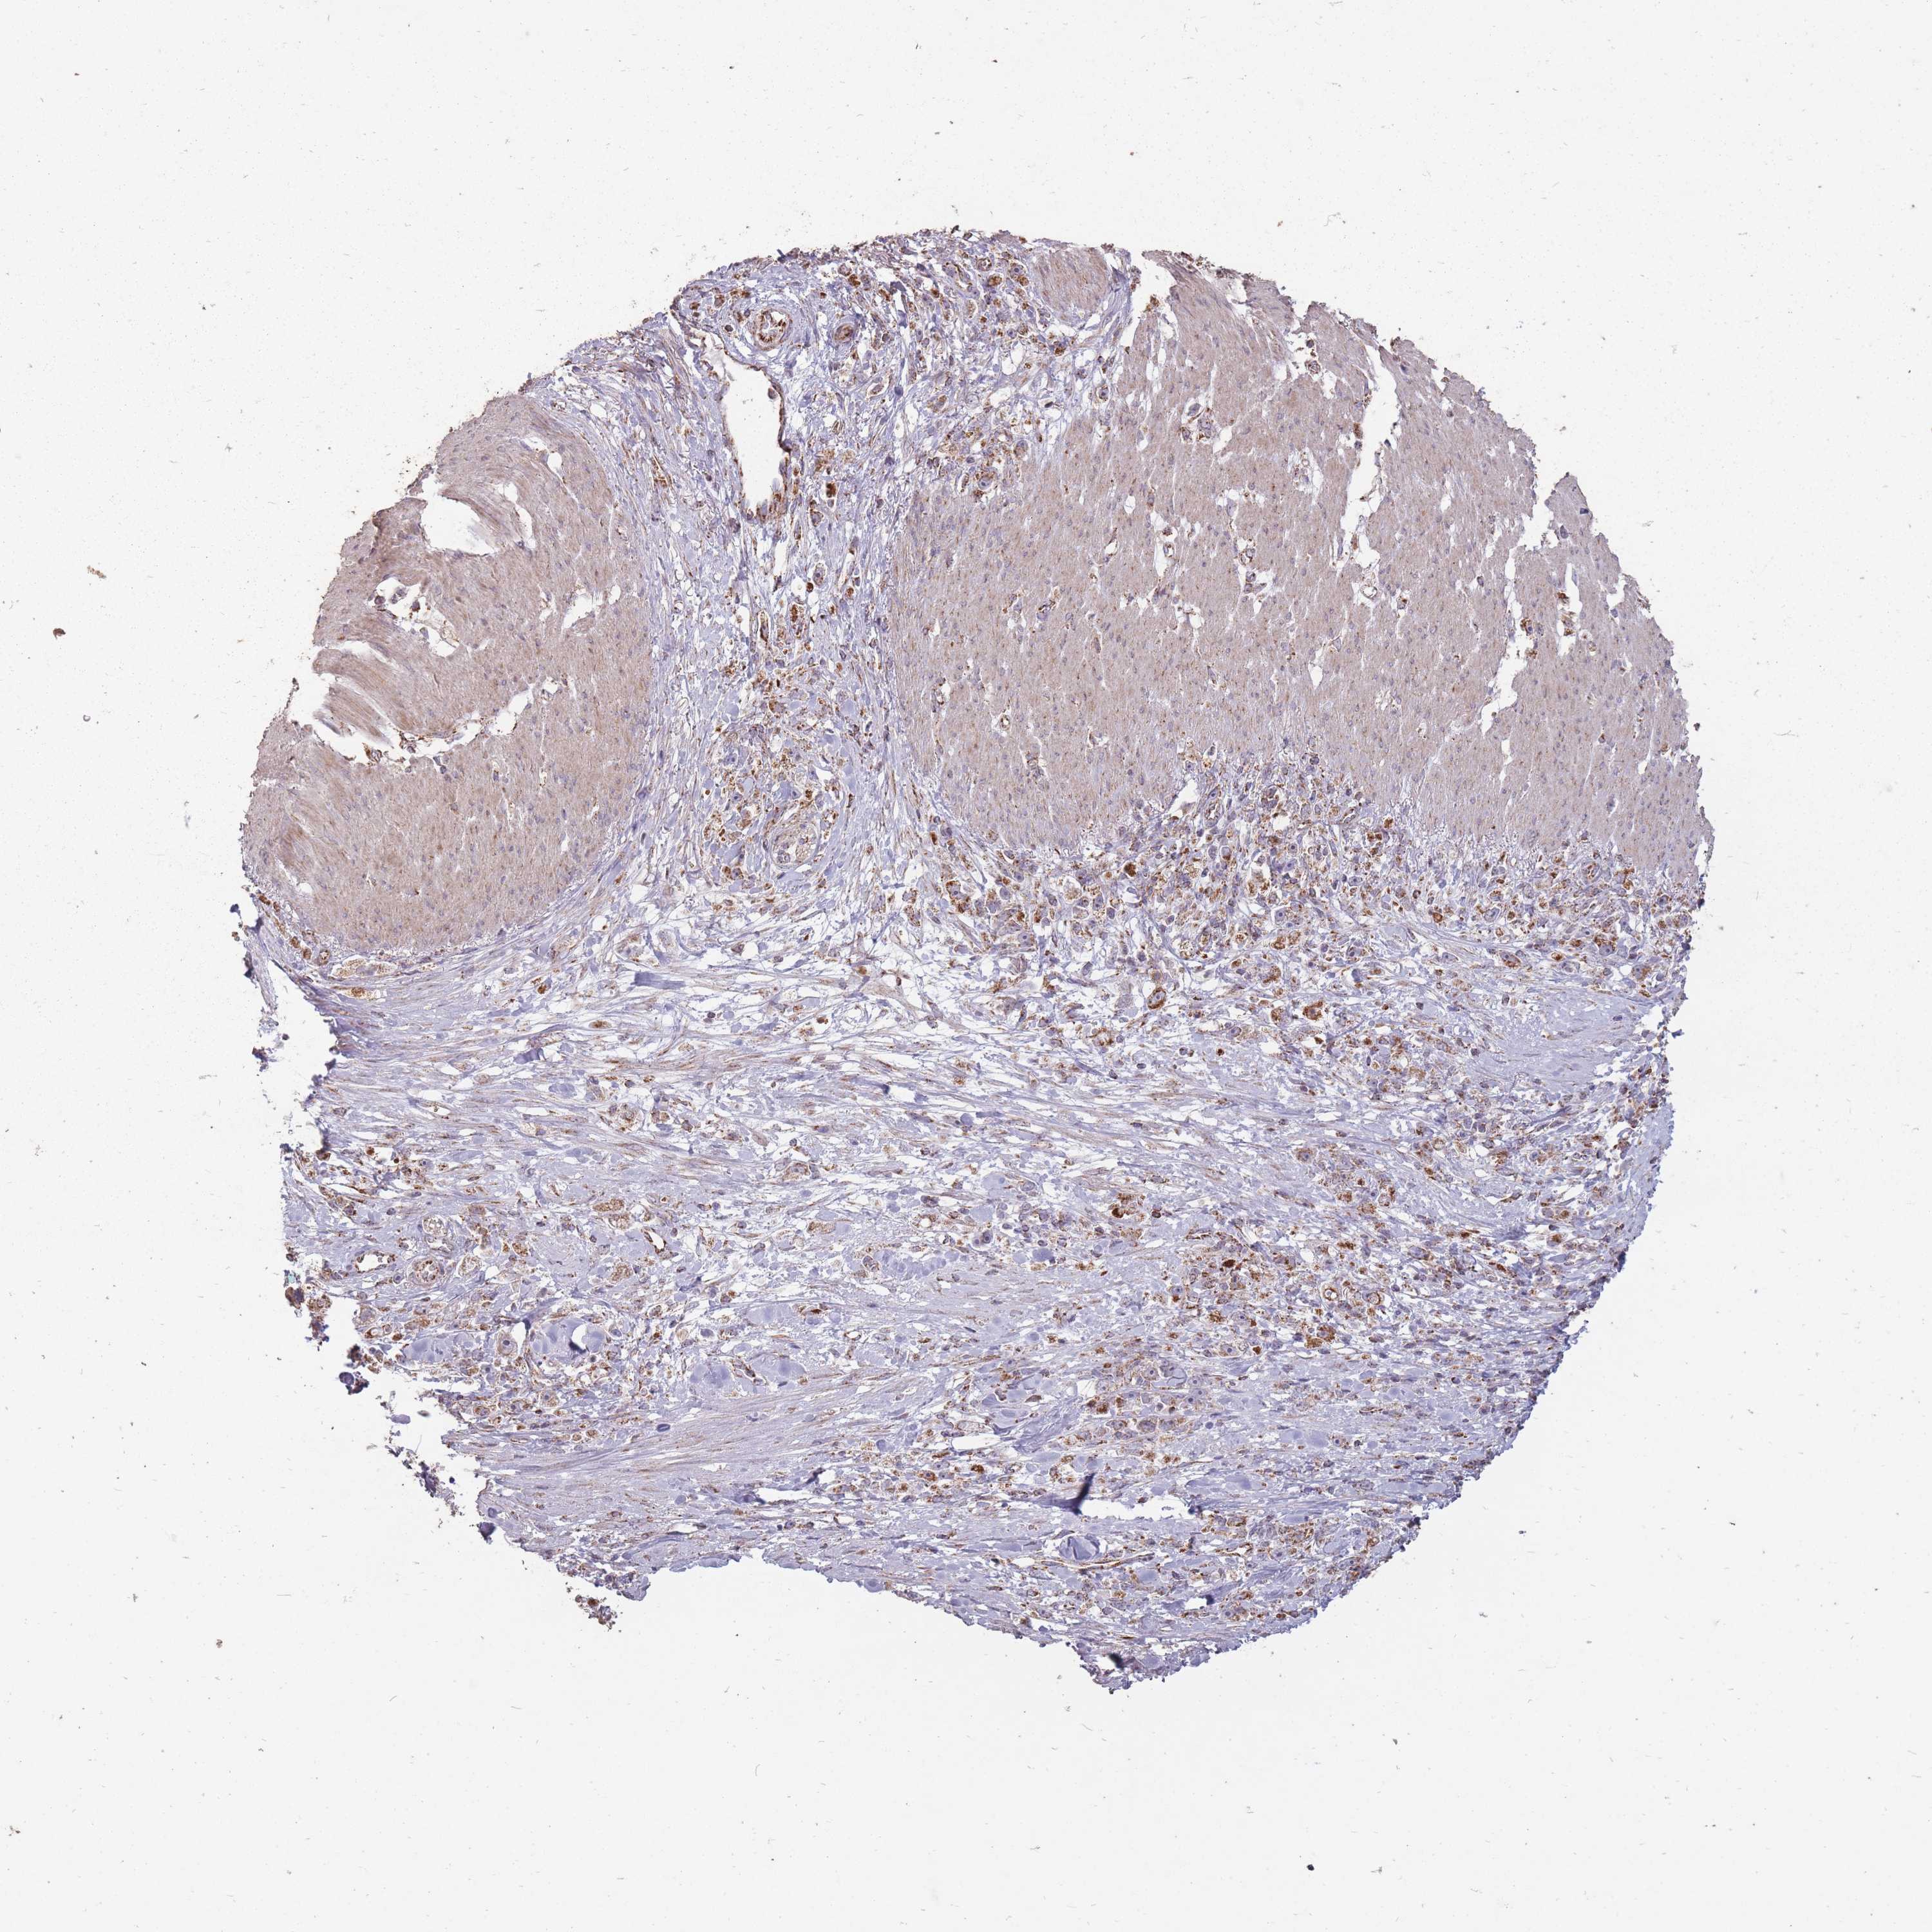

STOMACH CANCER - Protein expressioni

A mouse-over function shows sample information and annotation data. Click on an image to view it in a full screen mode. Samples can be filtered based on level of antibody staining by selecting one or several of the following categories: high, medium, low and not detected. The assay and annotation is described here.

Note that samples used for immunohistochemistry by the Human Protein Atlas do not correspond to samples in the TCGA dataset.

Antibody stainingi

Antibody staining in the annotated cell types in the current human tissue is reported as not detected, low, medium, or high, based on conventional immunohistochemistry profiling in selected tissues. This score is based on the combination of the staining intensity and fraction of stained cells.

Each image is clickable and will lead to virtual microscopy that enables deeper exploration of all samples and also displays staining intensity scores, fraction scores and subcellular localization as well as patient and tissue information for each sample.

Antibody HPA051398

Staining

High

Medium

Low

Not detected

Intensity

Strong

Moderate

Weak

Negative

Quantity

>75%

75%-25%

<25%

None

Location

Nuclear

Cytoplasmic/membranous

Cytoplasmic/membranous,nuclear

Adenocarcinoma, NOS